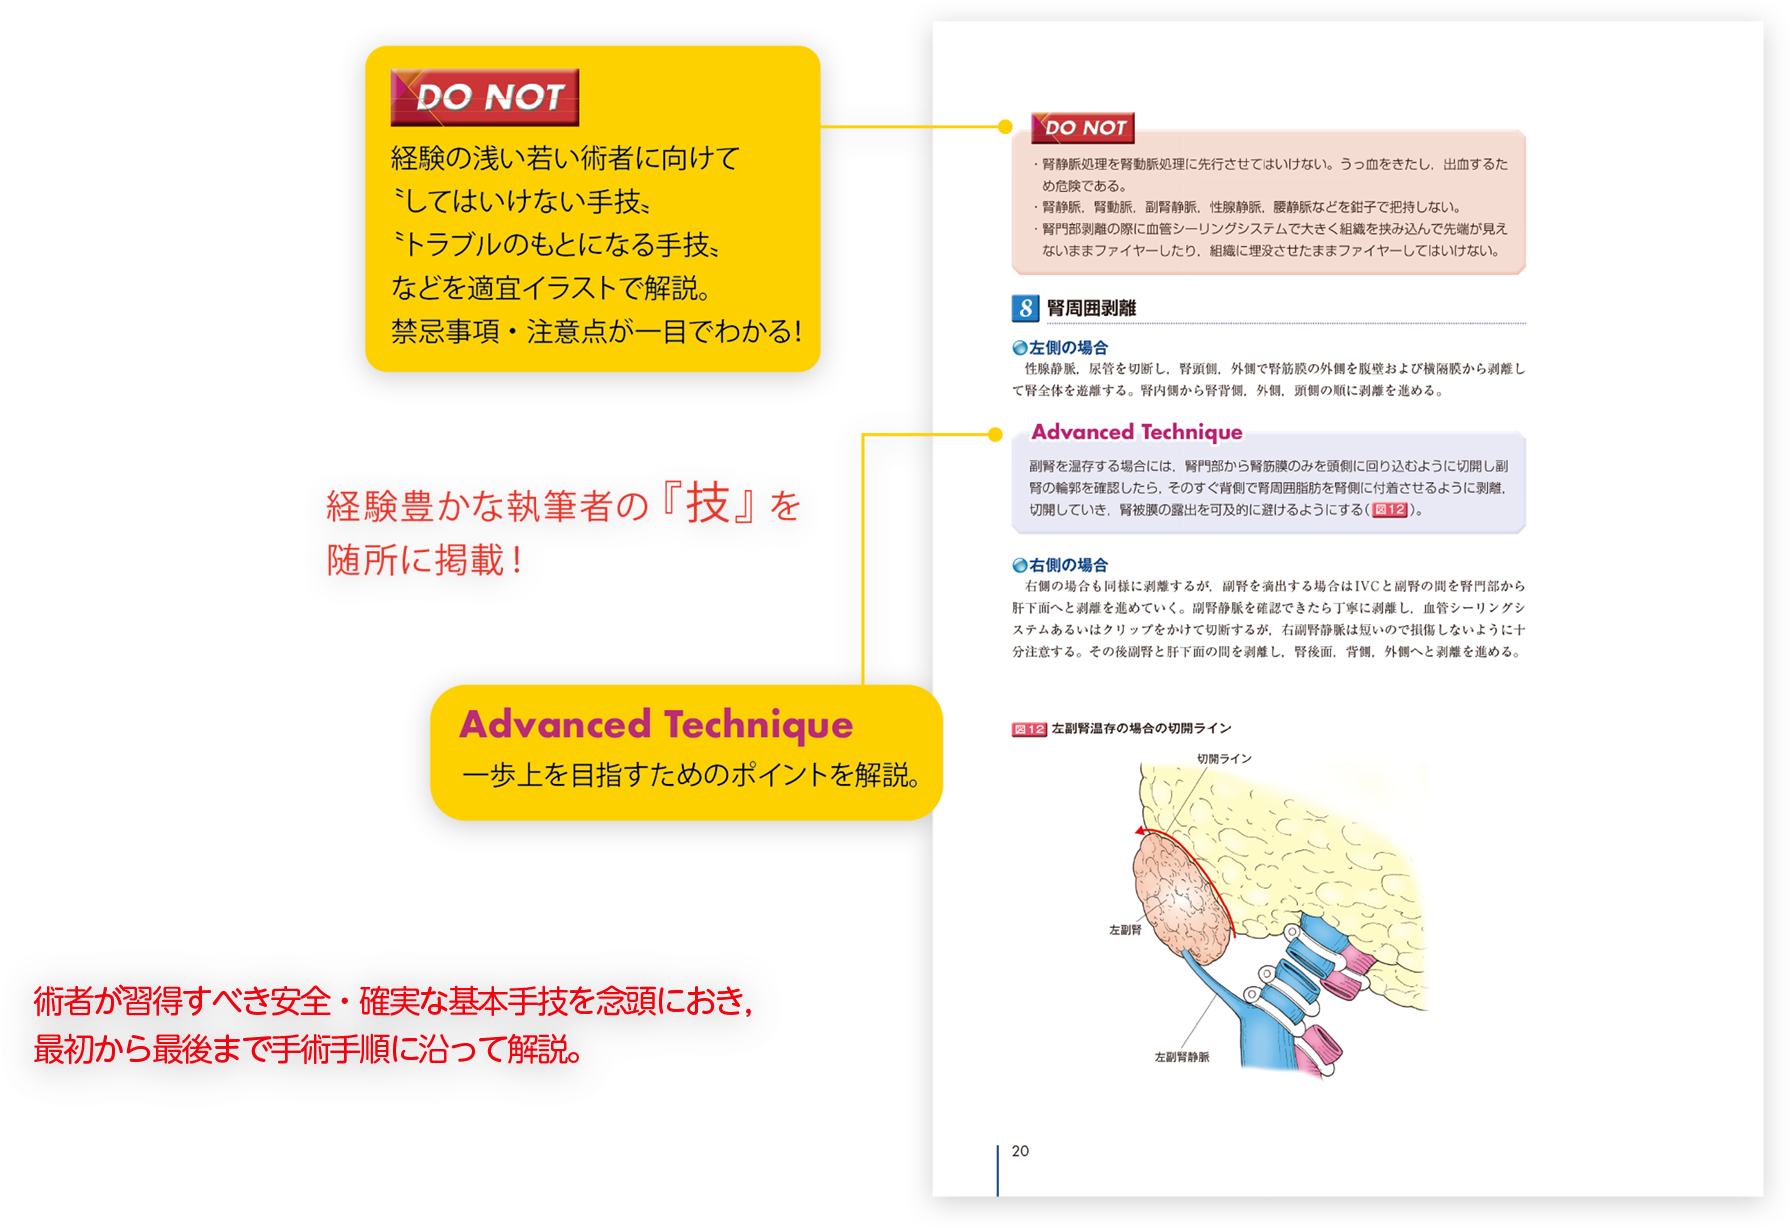

図解 泌尿器科手術【電子版】 | 医書.jp, メジカルビュー社 | Urologic Surgery Next,

m3電子書籍 | 手術 Vol.70 No.4 最新 肝胆膵高難度外科手術, メジカルビュー社 | Urologic Surgery Next,

メジカルビュー社 | Urologic Surgery Next, メジカルビュー社|小児外科|Urologic Surgery Next 7 小児,